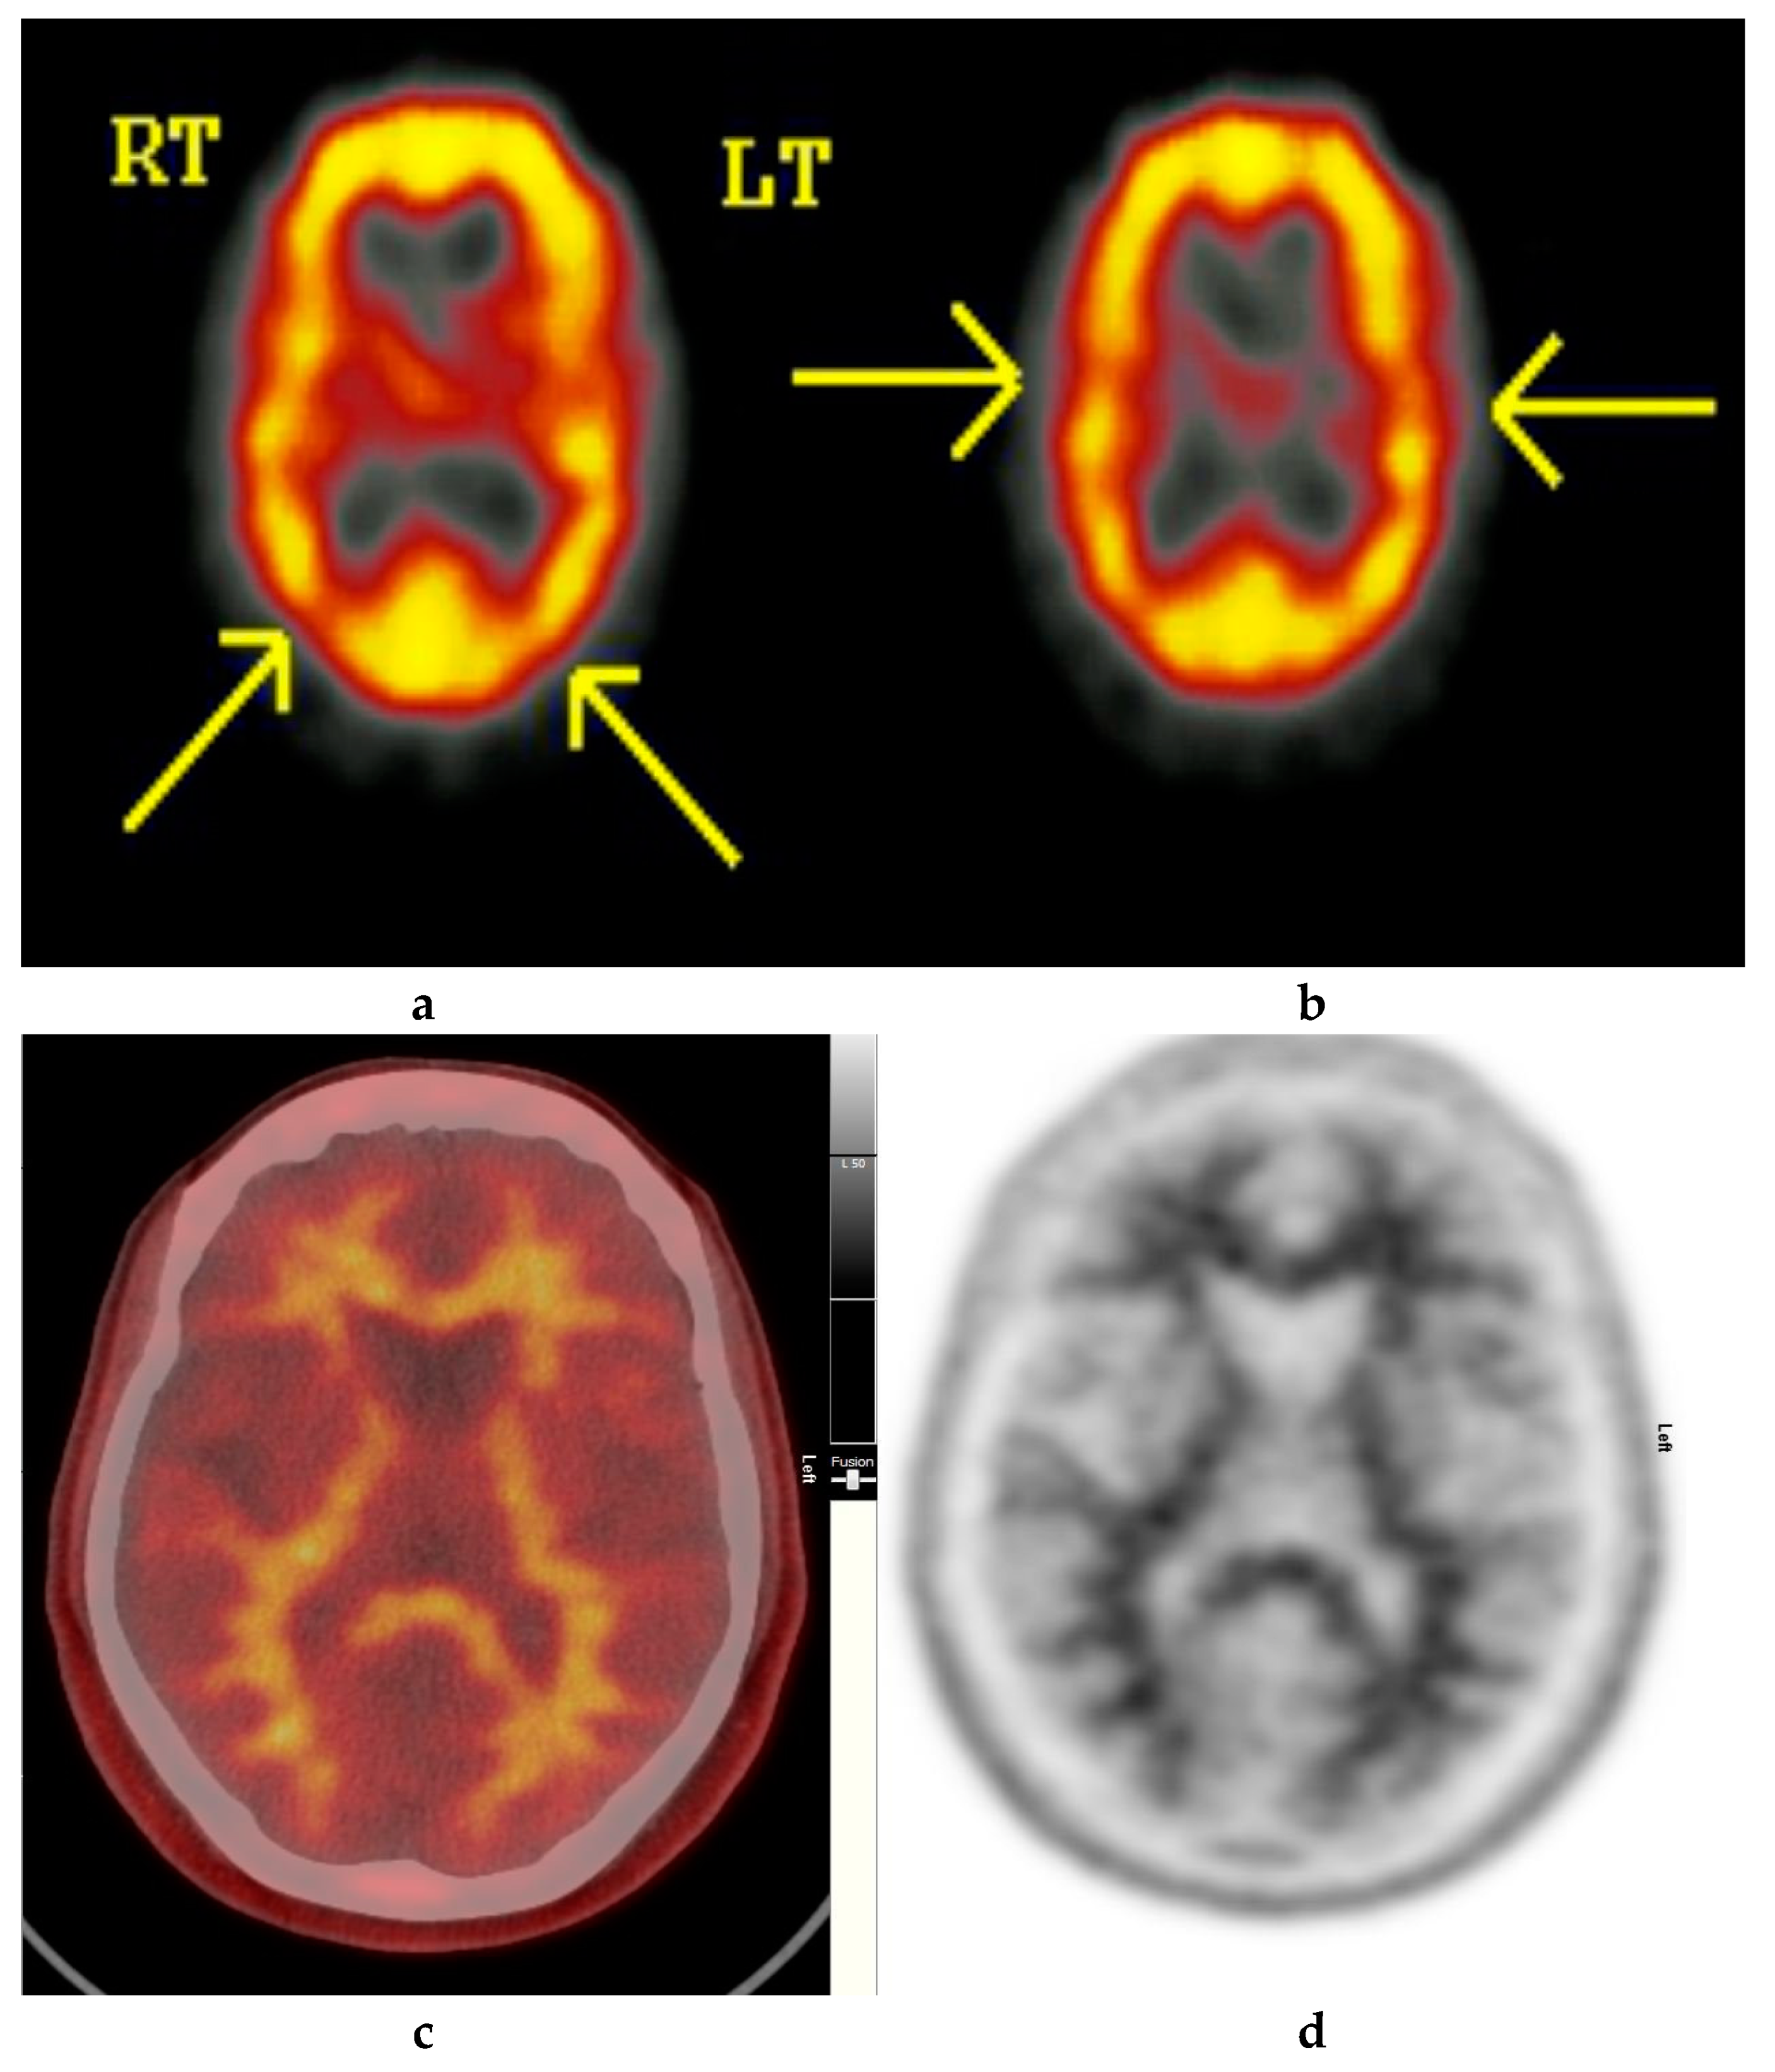

Normal study. Fifty-seven year old female patient memory problems/loss and confusion with a query of Alzheimer’s disease. (a) and (b) Technetium-99m HMPAO-SPECT brain Scan [99mTc]HMPAO-SPECT brain scan. Brain scan showed mildly reduced perfusion to both temporal and both parietal lobes (yellow arrows) with relatively better perfusion anteriorly. Reduction of cerebral blood flow in these regions is commonly seen in patients with early Alzheimer’s dementia rather than vascular dementia. However, in view of the subtle nature of the appearances on the [99mTc]HMPAO-SPECT brain scan, the [18F]FBP brain scan was performed to identify beta amyloid plaque disease and to give a higher confidence for AD diagnosis or suggest vascular aetiology. (c) Color coded [18F]FBP scan. (d) Grey scale [18F]FBP scan shows good contrast between grey and white matter in sections of the brain and no obvious evidence of beta amyloid plaque disease. This means that the likelihood of developing AD is low and as such the overall findings are more suggestive of vascular aetiology rather than early AD. (Figures are courtesy RLBUHT Hospital database).

Abnormal study. Sixty-eight year old female patient with speech difficulties, deficits in memory, and visuospatial abilities. (a) [99mTc]HMPAO-SPECT brain scan shows asymmetrical heterogenous reduced perfusion to both parietal and temporal lobes (worse on the left side) as with involvement of the frontal lobes identified by the yellow arrows. Normal areas of temporal perfusion were noted in between the abnormal parietal and frontal areas. In a patient with cognitive impairment, the findings indicate patterns of cerebral blood flow commonly seen in patients with mixed dementia, i.e., Alzheimer’s disease with vascular dementia. (b) Color coded [18F]FBP scan. (c) Grey scale [18F]FBP scans show loss of contrast between grey and white matter in all sections of the brain suggestive of beta-amyloid plaque deposition/disease. In conjunction with the [99mTc]HMPAO-SPECT brain scan, the overall findings are again suggestive of vascular as well as beta amyloid plaque disease (early AD), making the diagnosis mixed type AD. (Figures are courtesy RLBUHT Hospital database).